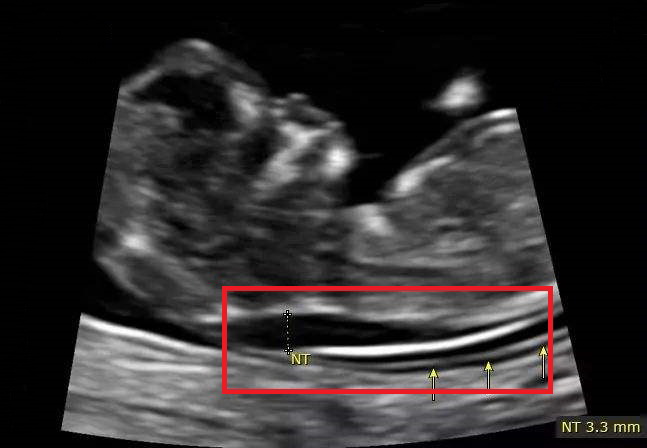

主要是通过B超检查胎儿颈部透明层较厚的部位,用于早期诊断胎儿是否存在唐氏综合征等染色体疾病及其他发育异常。

通常情况下,NT检查必须要在孕11~13周+6天之间进行——若早于孕11周,胎儿过小,机器难以扫描出其颈部透明带厚度;若晚于孕13周+6天,颈部透明带的淋巴液可能被胎儿正在发育的淋巴系统吸收,导致结果不够准确。

NT检查会有一个确定的诊断结果:通常情况下,当NT值低于2.5mm时判断为正常,说明胎儿生长发育没有出现异常;当大于或等于2.5mm可判断为胎儿颈部透明带增厚,且检查值越高,说明增厚越明显,胎儿异常的几率及异常程度也就越高。

据多种研究结果表明:当NT值大于3mm时,胎儿异常率增加10%,当大于6mm,胎儿正常的几率仅为10%,其余90%则为异常胎儿。